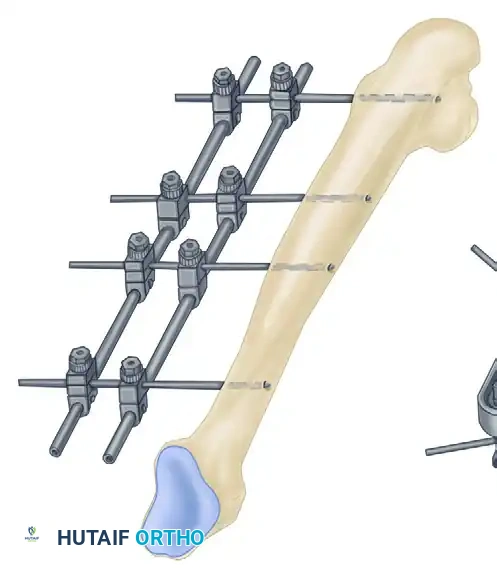

The Femur

- Distal Femur: The safe zone is strictly lateral or anterior. Medial pins risk injury to the superficial femoral artery and vein in the adductor canal.

- Proximal Femur: Pins are typically placed laterally, aiming toward the lesser trochanter, avoiding the femoral neurovascular bundle anteriorly and the sciatic nerve posteriorly.

- Evaluate orthogonal radiographs to determine fracture geometry and plan pin placement. Ensure pins are placed at least 1.5 to 2 cm away from the fracture lines to avoid propagating cracks.